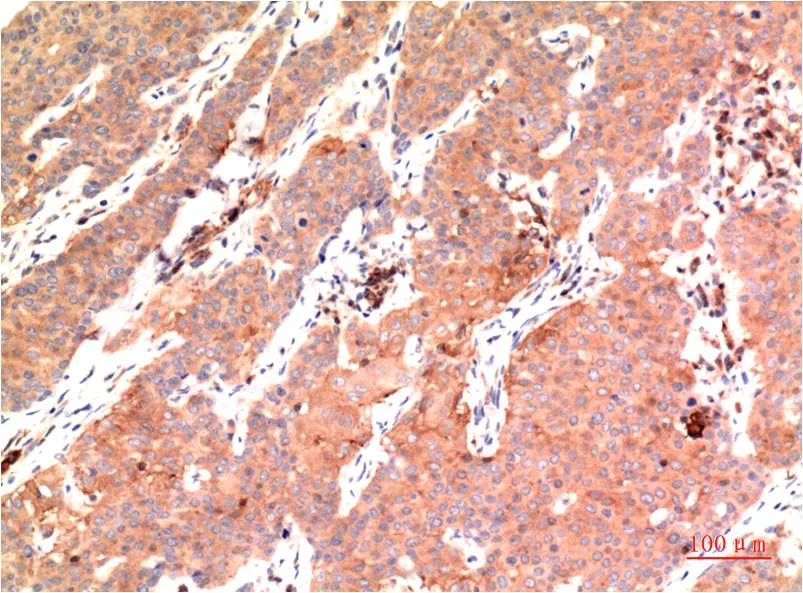

IKB beta (5H3) Mouse Monoclonal Antibody

Cat: AMM00735

Size1:50μL Price1:$150

Size2:100μL Price1:$280

Size3:500μL Price1:$280

Application:IHC-P

Reactivity:Human,Rat,Mouse

Conjugate:Unconjugated

Gene Name:NFKBIB